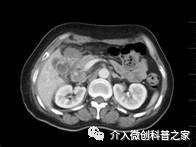

中晚期腺癌内部放射性粒子近距离照射治疗

(近距离照射杀死癌细胞、止痛效果好)